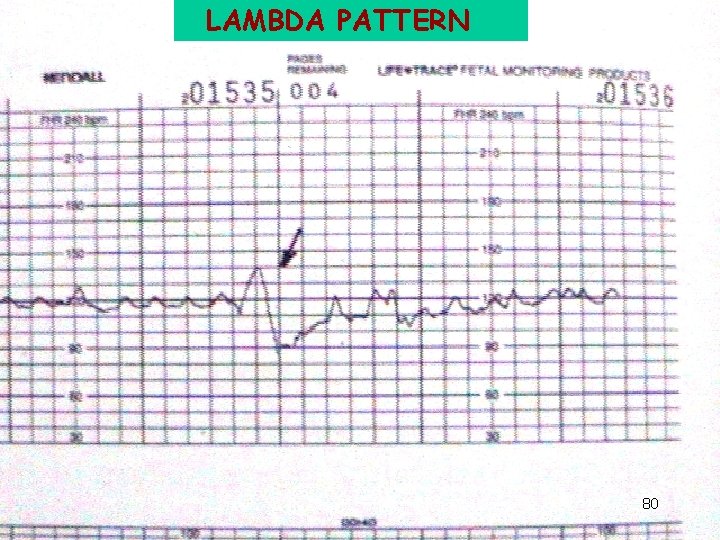

LAMBDA PATTERN 80